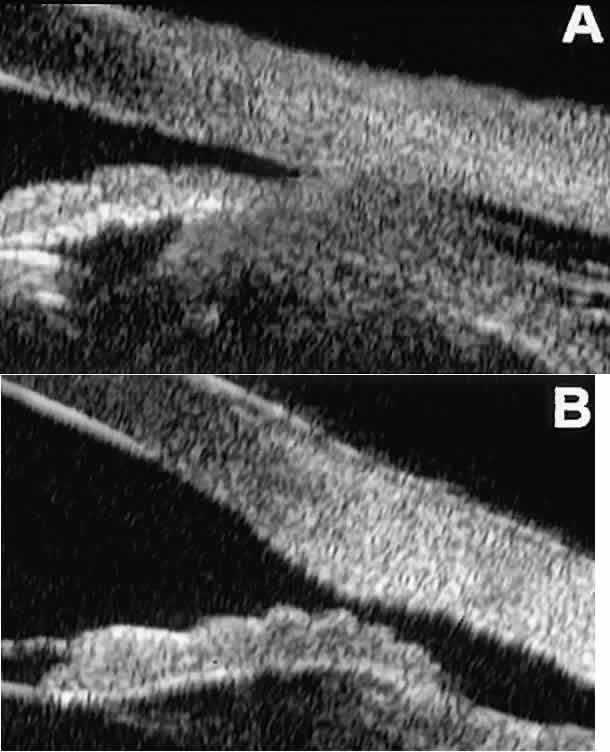

Postoperative UBM imaging of the anatomic changes caused by glaucoma surgery often helps to explain mechanisms of success and failure of the various surgical procedures (Fig. 12).3,4 After laser iridotomy, UBM can show whether the iridotomy is partial thickness (see Fig. 12A) or full thickness (see Fig. 12B) and whether the plane of curvature of the peripheral iris has changed compared with the pretreatment findings. After trabeculectomy (see Fig. 12C), UBM can show whether the scleral aperture is patent or blocked internally, whether the peripheral iridectomy is open or blocked, and whether the filtering bleb is flat, shallow, or deep.9 After tube shunt surgery (see Fig. 12D), UBM can show the position of the tip of the tube and whether its orifice is open or plugged.

Fig. 12. UBM features in glaucomatous eyes after treatment or filtering surgery. A. Incomplete peripheral iridectomy created by laser. B. Full-thickness peripheral iridectomy created by laser. C. Postoperative features of trabeculectomy including peripheral iridectomy, inner scleral defect, thin residual scleral flap, and overlying conjunctival filtering bleb. D. Tube shunt projecting radially into anterior chamber; note that the tube “shadows” deeper structures.